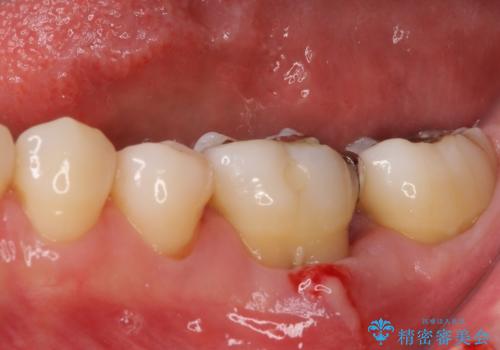

欠損部の歯肉が窪んでいるため、歯肉移植により形態を改善し、オールセラミックブリッジにて補綴することとしました。

事前に装着されていた接着タイプのブリッジは、歯の切削量が少ない反面、接着界面から虫歯が進行しやすく、脱落リスクが高くなるというデメリットがあります。

- 外科手術のため、術後に痛みや腫れ、違和感を伴います